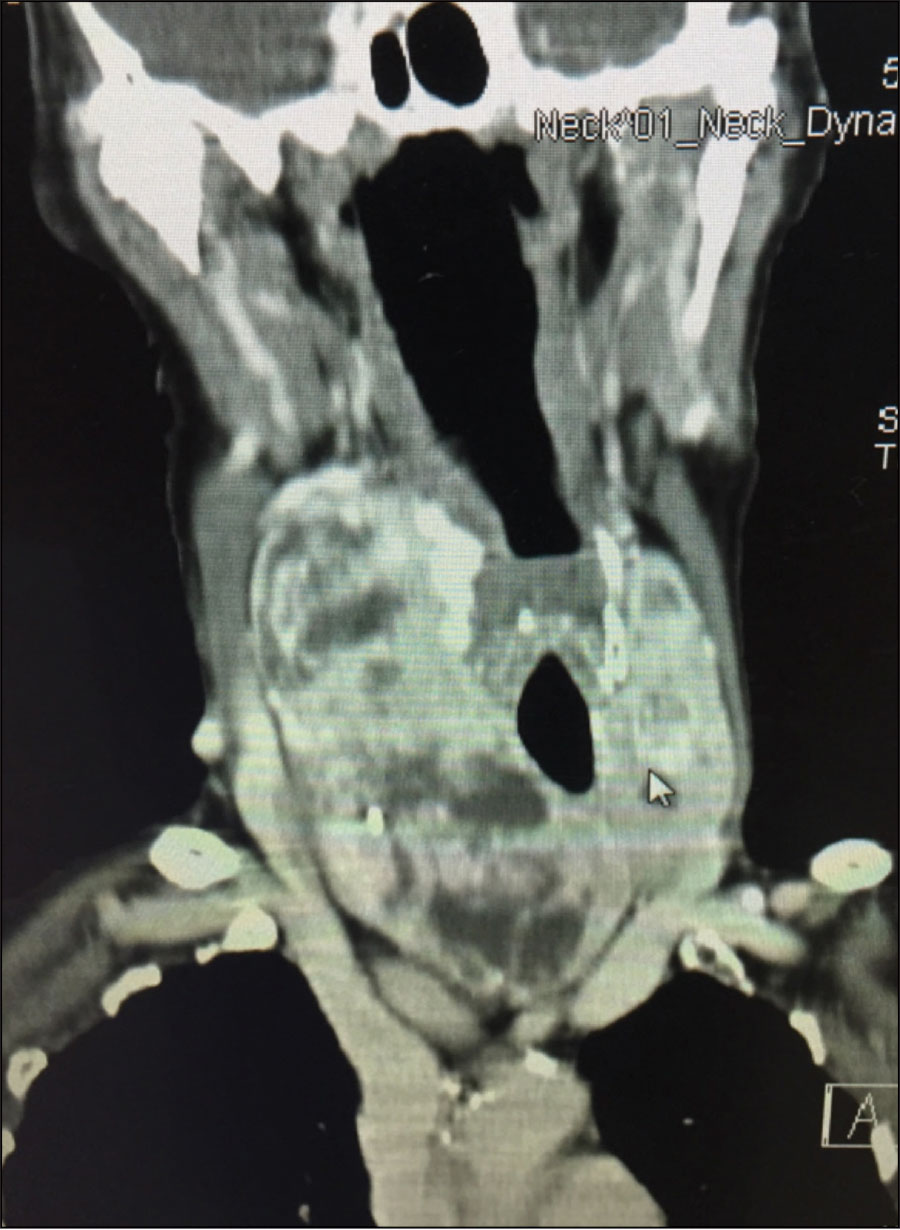

Figure 2. Large well differentiated thyroid cancer in the setting of a multinodular goiter

Figure 2. Large well differentiated thyroid cancer in the setting of a multinodular goiter(click to enlarge)